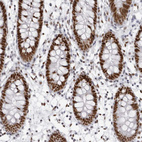

Immunohistochemical staining of human endometrium shows moderate nuclear positivity in glandular cells.